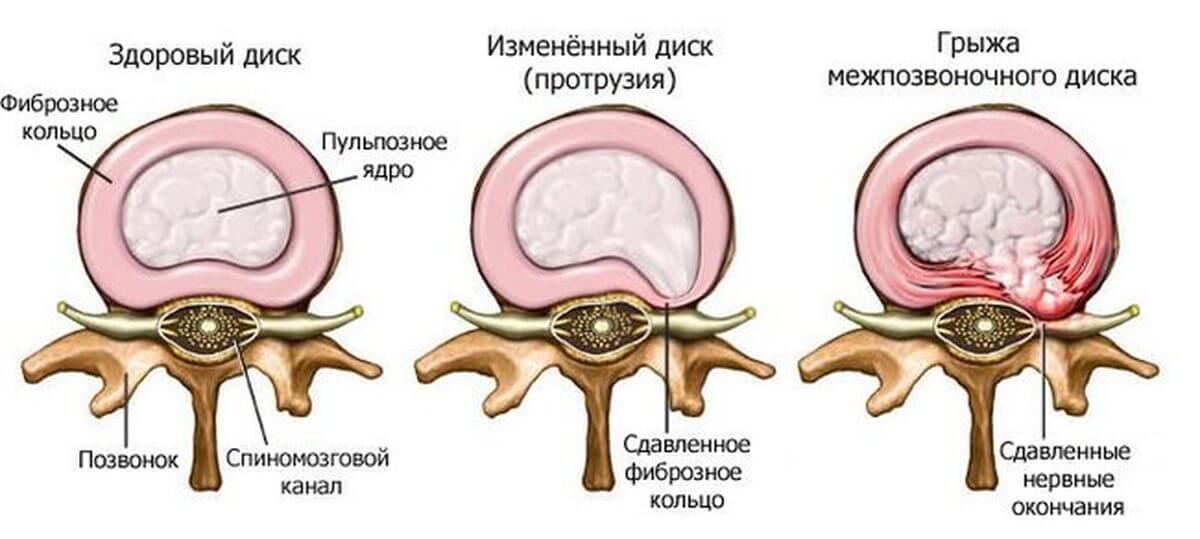

Причины заболевания

Межпозвоночные диски расположены между позвонками и выполняют функцию амортизаторов во время движения и сильной нагрузки на спину. Состоит межпозвоночный диск из ядра – желеобразная субстанция, накапливающая воду, и кольца сухожилий, расположенного вокруг ядра. Во время наклонов происходит сжимание дисков с выталкиванием ядра наружу. Когда диски крепки, то структурных деформаций не происходит. Но в случае нарушений, недостаточной прочности костной ткани происходит сильное продавливание кольца ядром. Кольцо растягивается, это место растяжения называется протрузия. Это первый этап на пути образования грыжи. Со временем под действием нагрузок кольцо разрывается, и ядро выпадает наружу, сдерживаемое лишь эластичной оболочкой. Это и есть межпозвоночная грыжа.

Грыжа позвоночника имеет выраженную симптоматику и сопровождается сильными болями. Это связано с тем, что позвоночный диск становится тоньше, в результате позвонки трутся друг о друга, что причиняет боль. Сама грыжа давит на нервные окончания, вызывая спазмы и онемения.